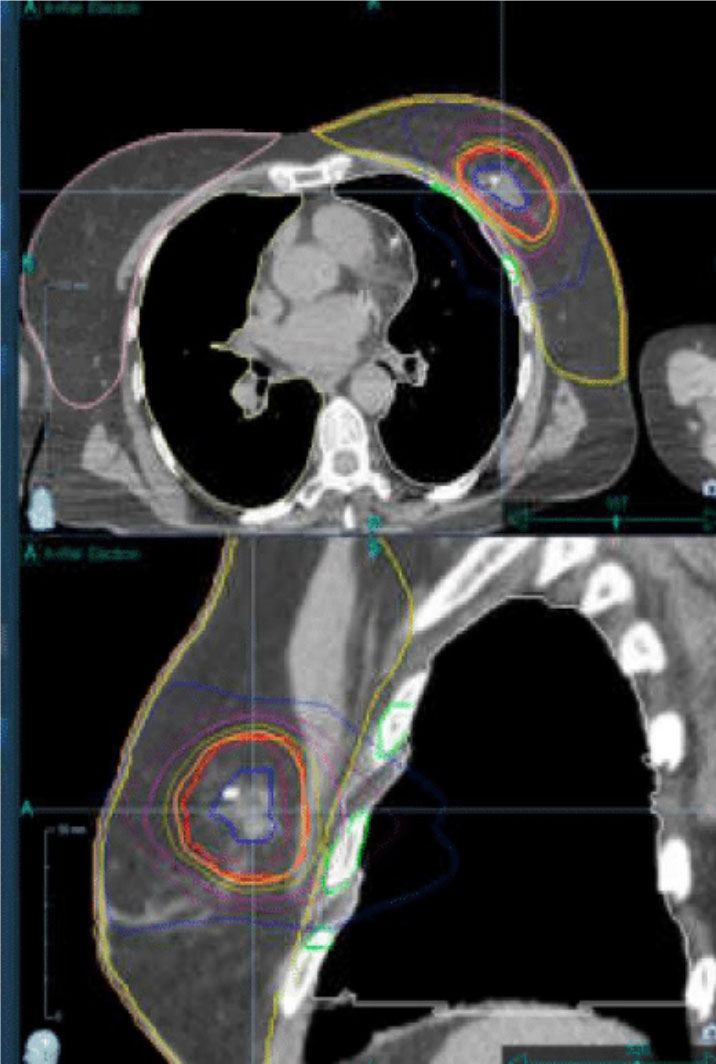

Capital Radiosurgery Centers (CRC) provides highly precise, non-invasive breast cancer treatment using advanced radiation technologies such as stereotactic radiosurgery (SRS), stereotactic body radiation therapy (SBRT), and intensity-modulated radiation therapy (IMRT). Each treatment plan is developed based on clinical appropriateness and delivered by a specialized team of board-certified radiation oncologists, medical physicists, dosimetrists, and oncology-trained nursing and support staff.

These advanced therapies precisely target the tumor area while minimizing radiation exposure to surrounding healthy tissue, including the heart and lungs. Treatment is delivered in a comfortable outpatient setting, allowing patients to receive advanced cancer care close to home without surgery or hospitalization.

SBRT is an advanced radiation therapy that targets tumors with sub-millimeter accuracy. Unlike conventional radiation, which may take weeks, SBRT completes treatment in days—protecting healthy tissue and helping patients maintain their daily routines.

Technology Designed for Precision

We use CyberKnife® and Varian TrueBeam® to treat tumors anywhere in the body, even those that move with breathing or normal motion. Advanced imaging and real-time tracking mean no restrictive frames, no breath-holding, and no invasive procedures.